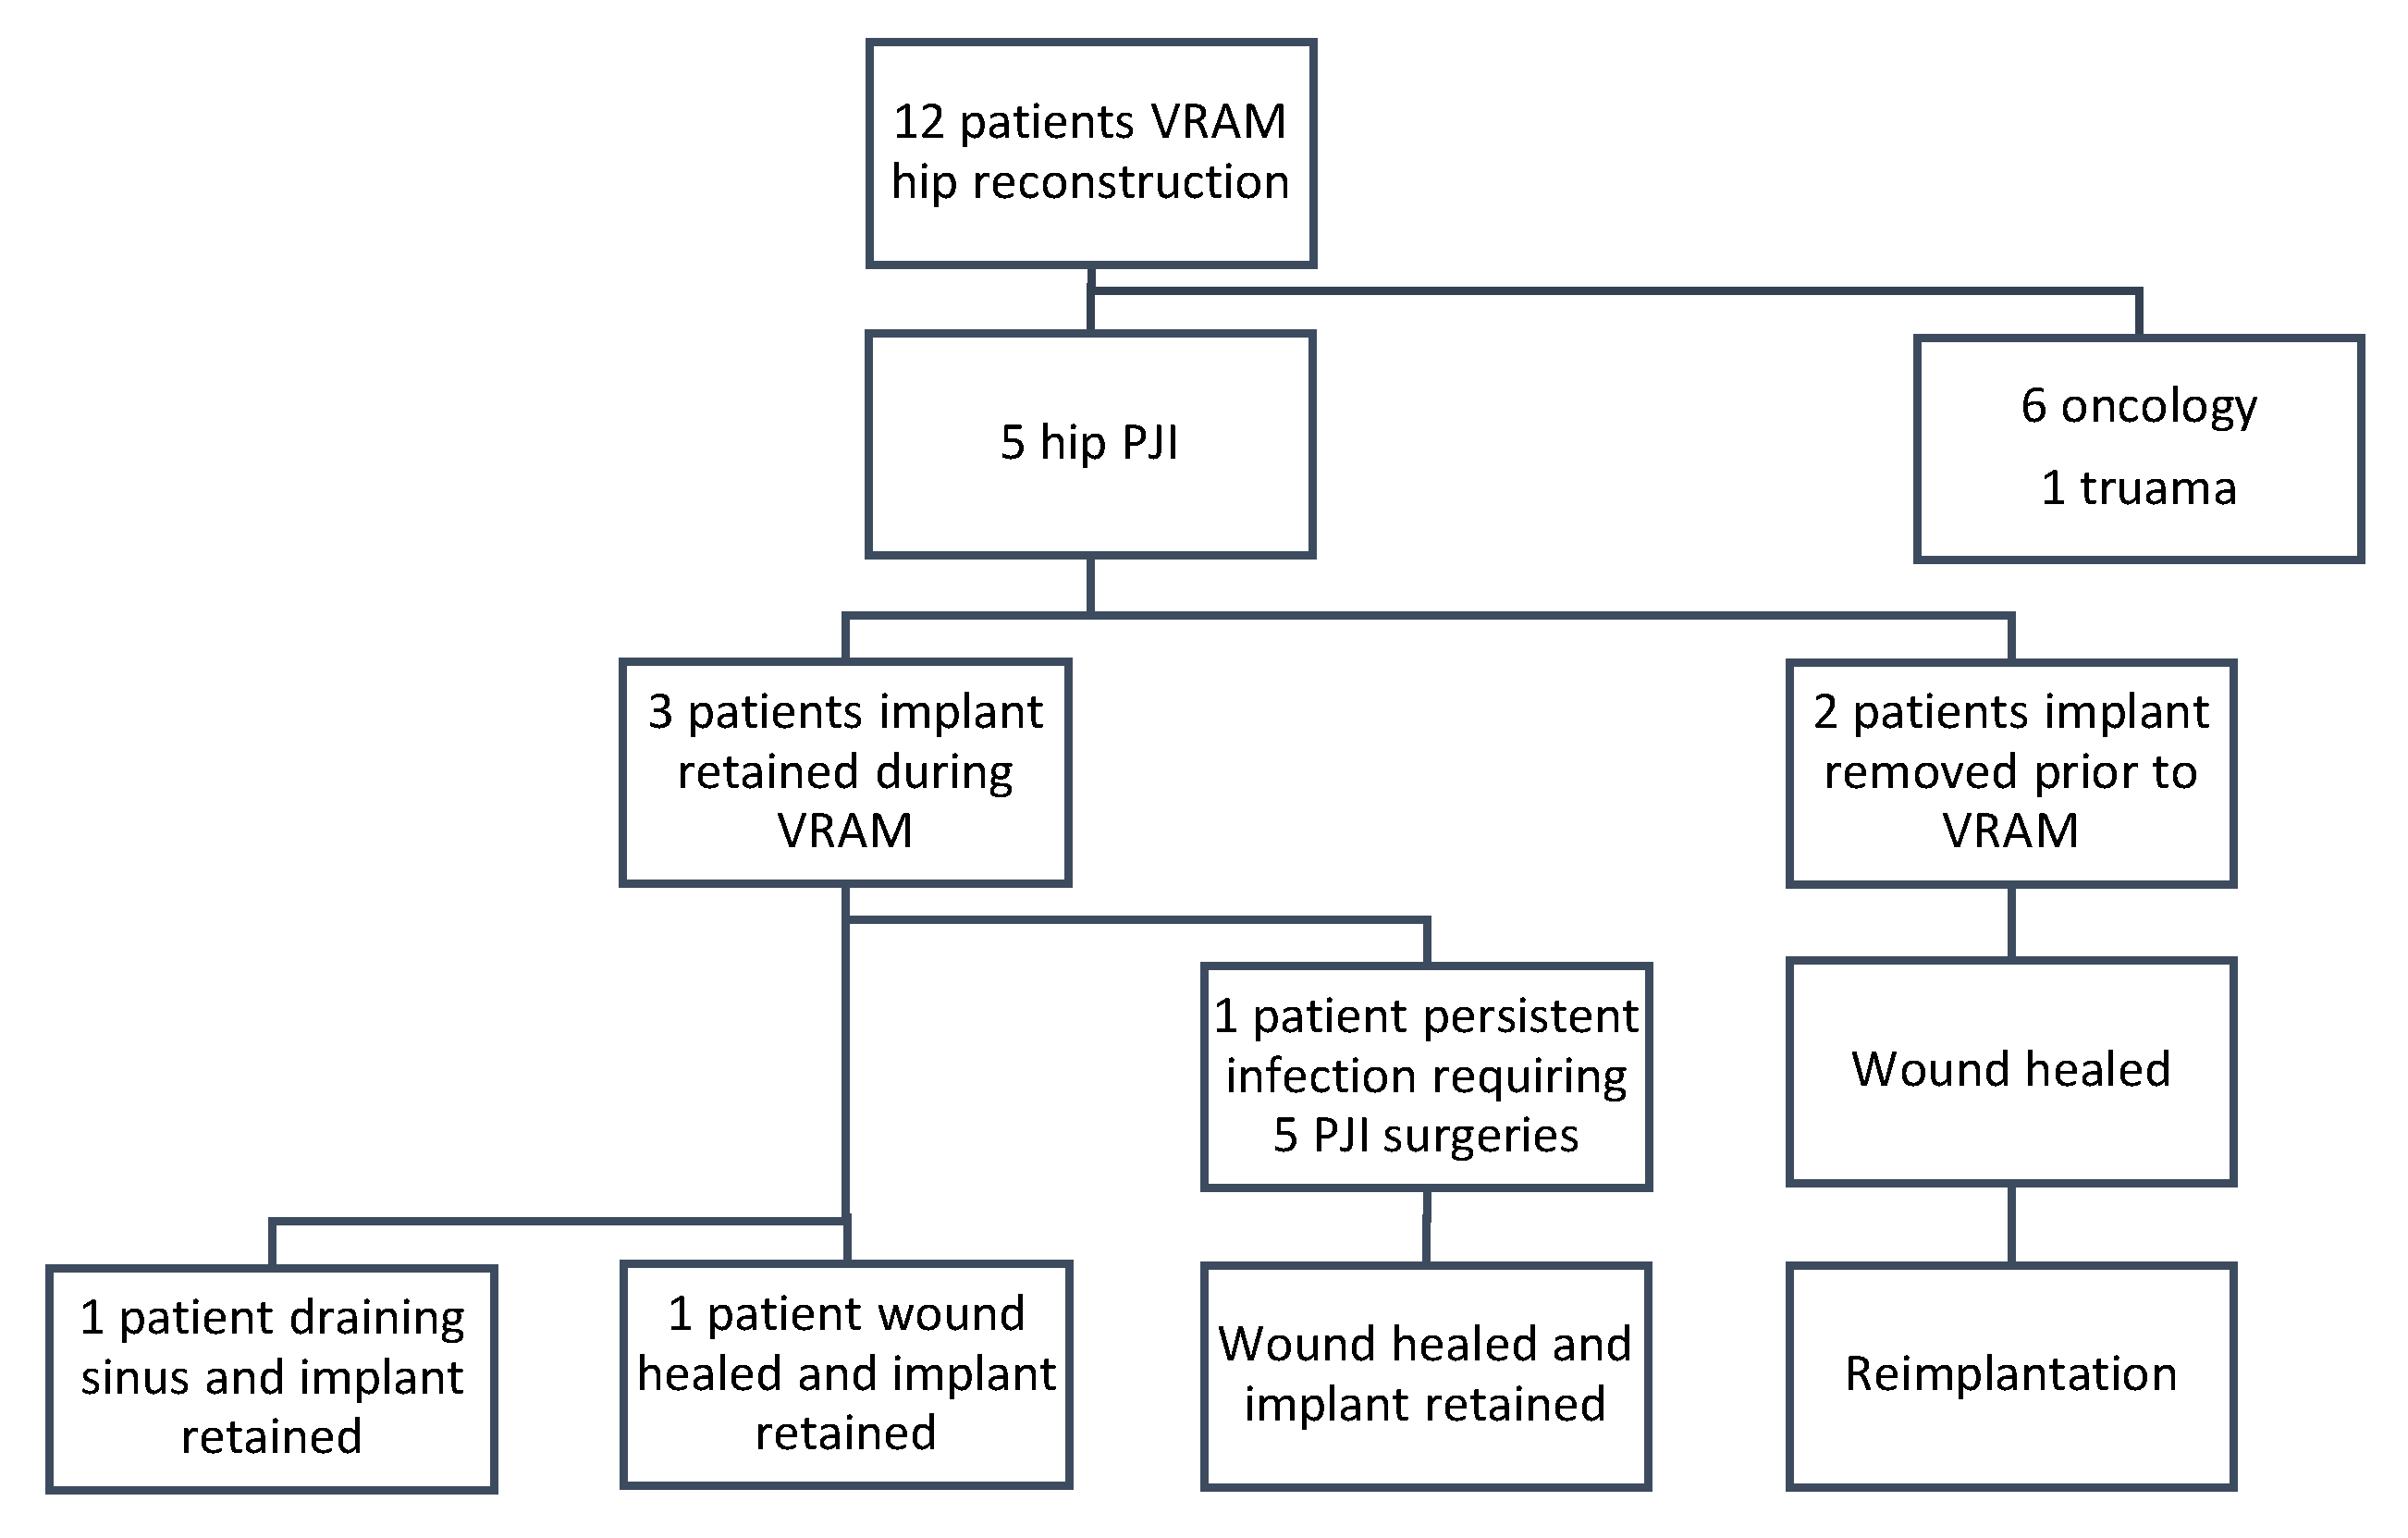

3. Results

3.1. Patient Characteristics and Surgical History

3.2. Surgical Outcomes, Complications, and Functional Outcome